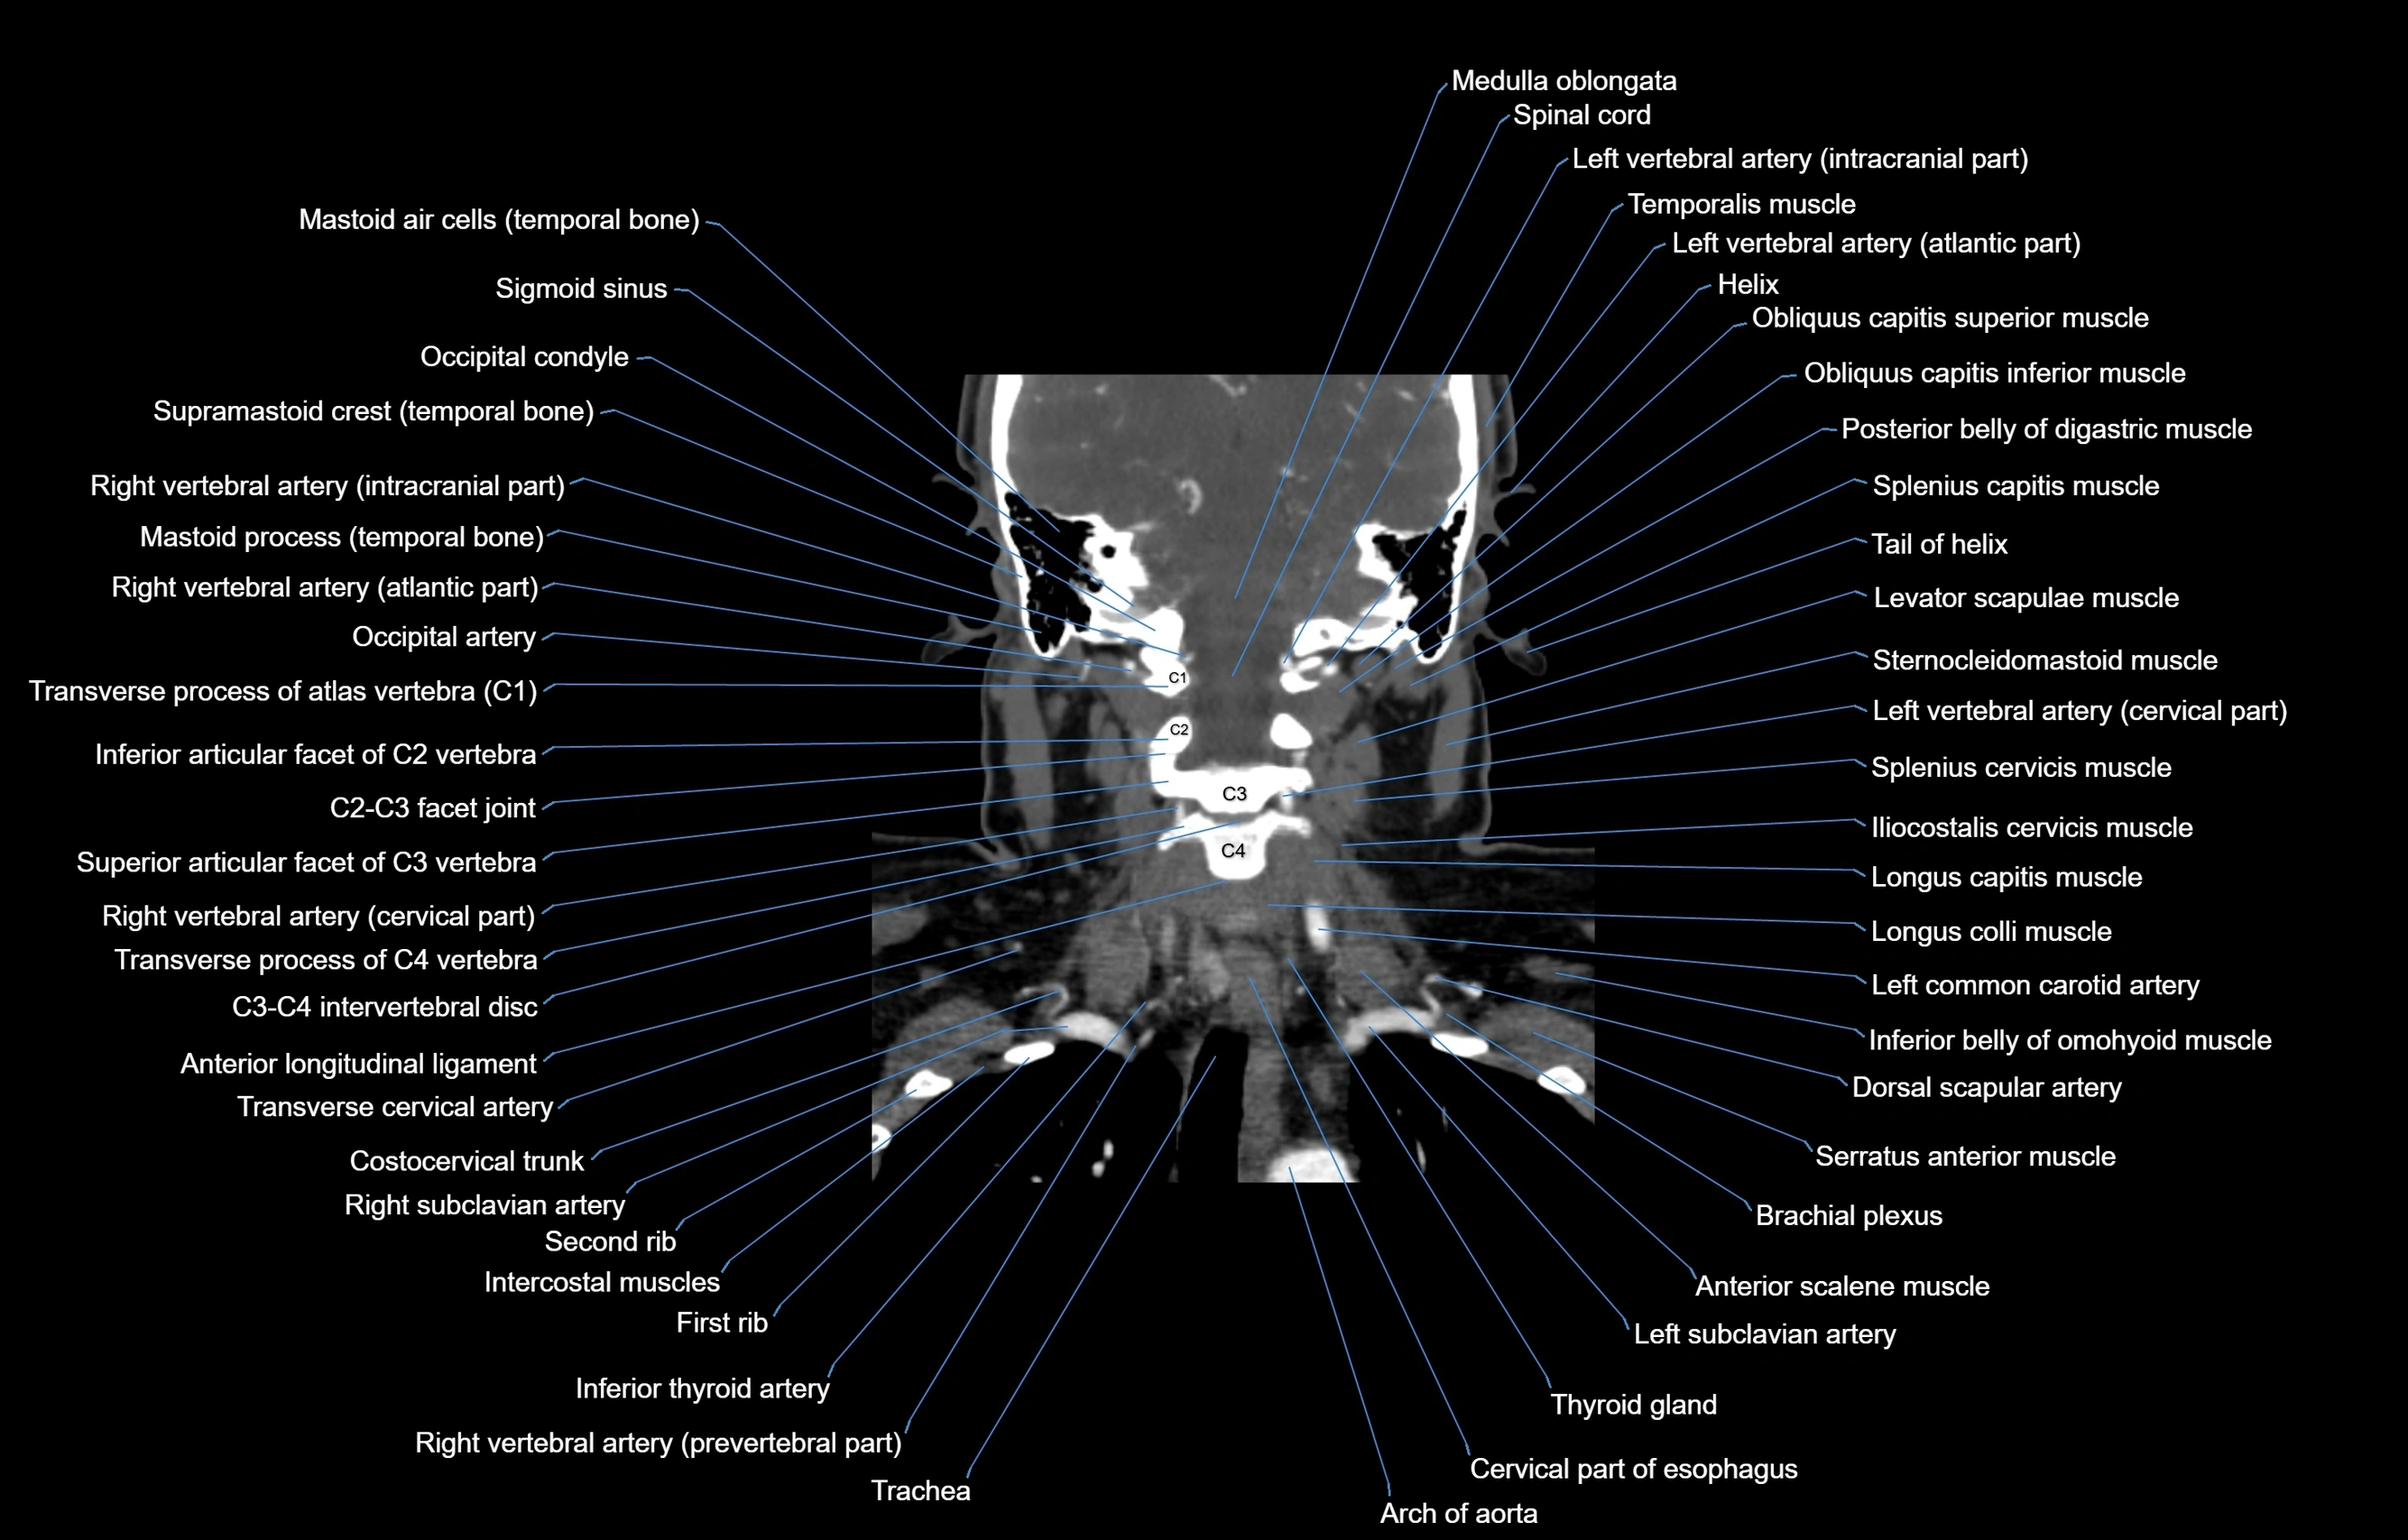

- Anterior longitudinal ligament

- Brachial plexus

- Cervical part of esophagus

- Dorsal scapular artery

- Iliocostalis cervicis muscle

- Inferior belly of omohyoid muscle

- Inferior thyroid artery

- Left common carotid artery

- Left subclavian artery

- Left vertebral artery

- Left vertebral artery (atlantic part)

- Left vertebral artery (cervical part)

- Longus capitis muscle

- Longus colli muscle

- Right vertebral artery

- Right vertebral artery (atlantic part)

- Right vertebral artery (cervical part)

- Spinal cord

- Trachea

- Transverse cervical artery